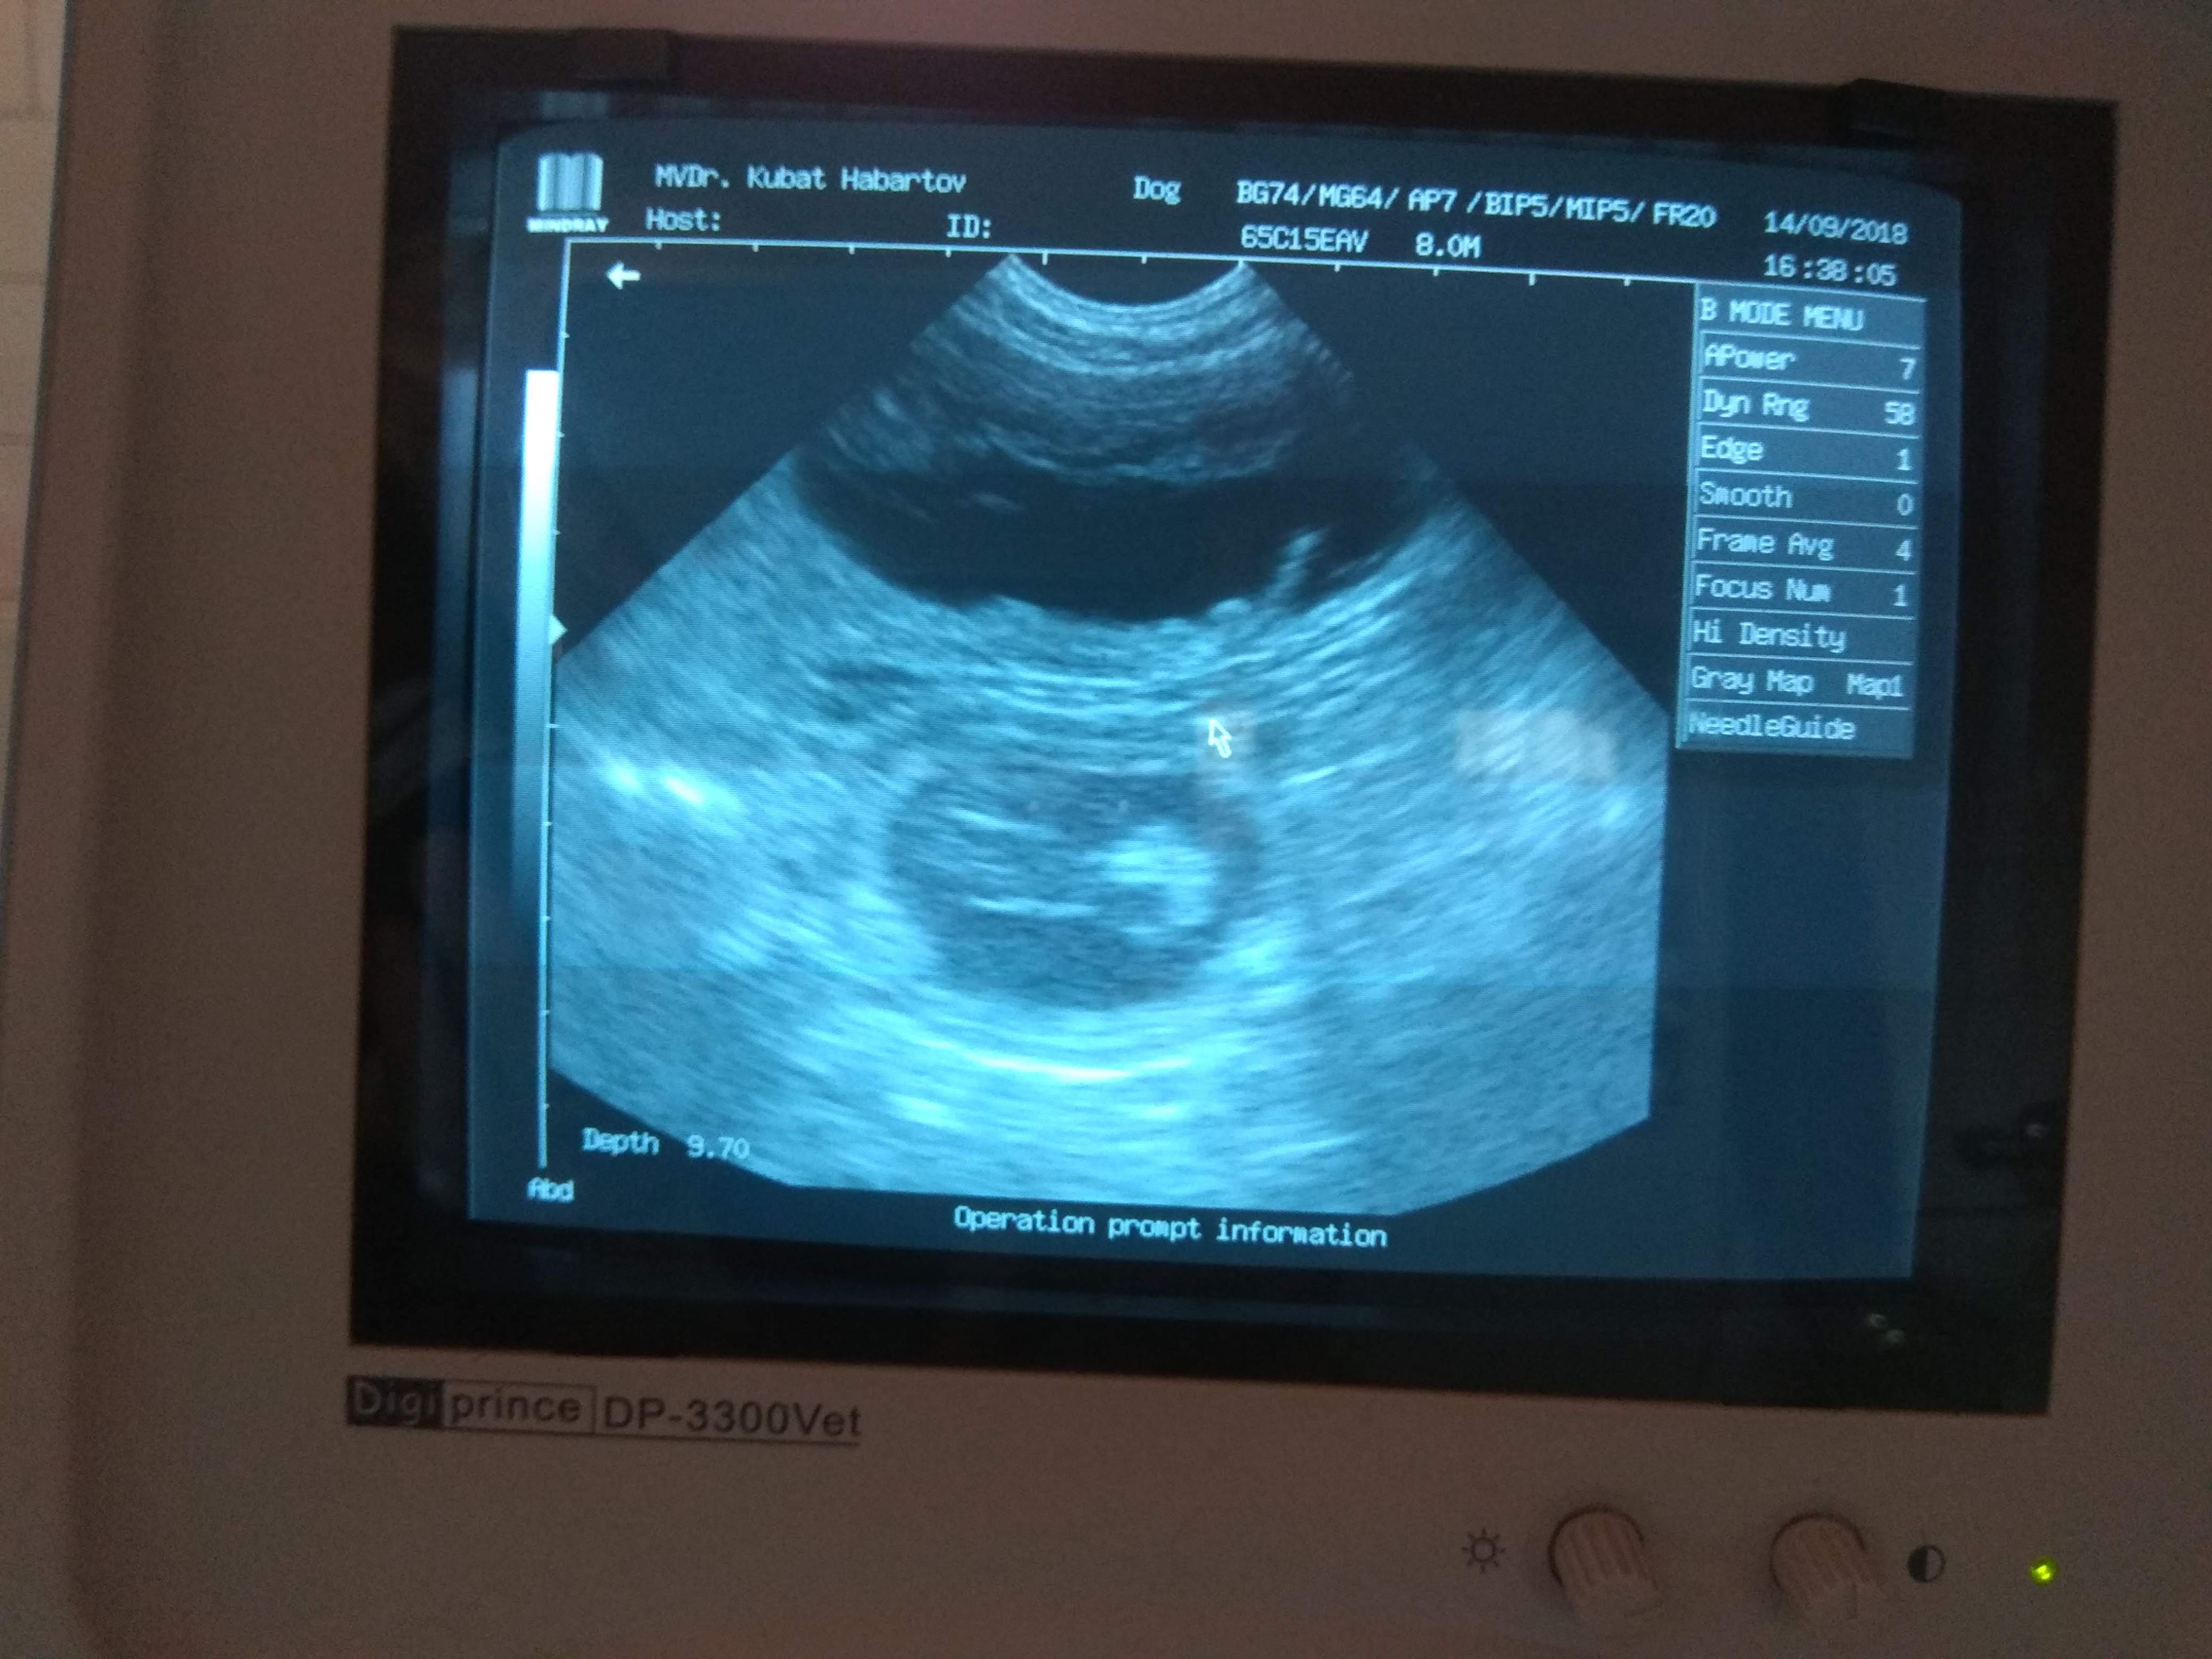

Dne 14.9.2018 nám byla potvrzena březost naší fenky Oradea Kráľovská Stráž. Hrdým otcem je celočerný pes Gino des Trois Petit Diables.

Štěňátka by se měla narodit kolem poloviny října.